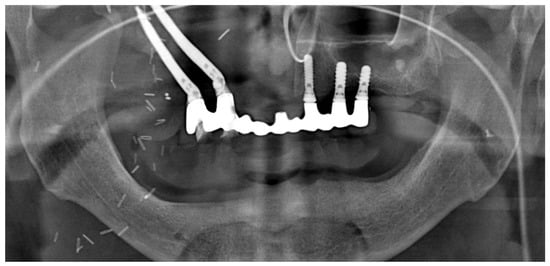

No post-operative complications were seen, and the patient was discharged from the hospital after 10 days. The patient was able to return to a normal diet (solid) after just 7 days following surgery, with no further complaints regarding function or pain, apart from the residual swelling caused by the intervention (Figure 16 shows the orthopantomogram view of the rehabilitation 7 days after surgery). Figure 16 shows the provisional prosthesis in place at 7 days follow-up (Note on Figure 16: In the radiological view, the provisional prosthesis shows some misfits with the implants on the right side of the maxilla (second quadrant). This is because it was relined and was adapted with a thin layer of acrylic resin to provide a stable and precise fit bilaterally on the implants).

Figure 16.

Panoramic X-ray at 7 days after surgery.

The occlusion and prosthesis were checked at a follow up on the 7th post-operative day. The patient underwent a cycle of radiotherapy without any complications or dehiscence of the flaps. The final fixed prosthesis was delivered 8 months after the surgical intervention. The definitive final removable prosthesis was retained by an implant-supported titanium bar that allowed the patient to have a strong and stable occlusion during function and provided easy access for oral hygiene. The patient reported a complete satisfaction from phonetic, functional, and aesthetic points of view. Figure 17a–d shows the final prosthesis (Note on Figure 17: The evolution of the oro-naso-sinusal defect repair through the soft tissue graft was uneventful without any complications. As can be seen in Figure 17, the tissue was œdematic for the first weeks and slowly shrank to healthy dimensions after healing).

Figure 17.

(a–c) Intra-oral occlusal and frontal view of the titanium bar retaining the definitive prosthesis and final prosthesis in occlusion. (d) Panoramic X-ray showing final prosthetic rehabilitation in place.